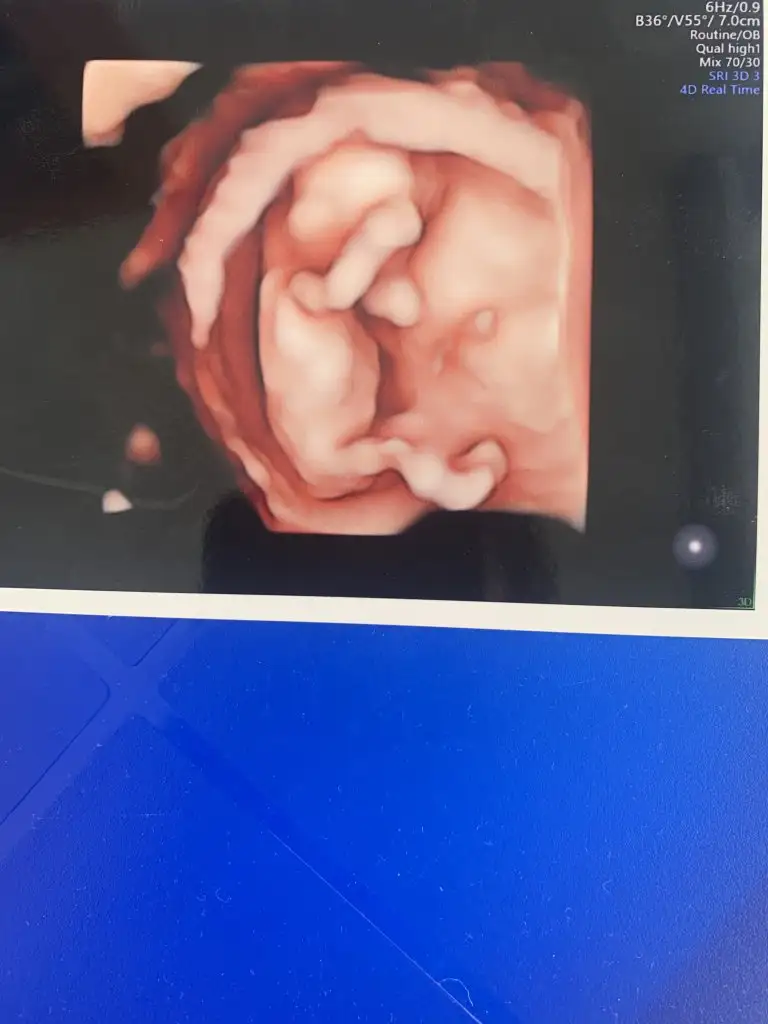

Kız değil mi14 haftalık bende tahmin alablrmiyim

Doktor daha belli değil dedi banada kız gbi geldi de öğrenemedm dahaKız değil mi

Daha belli değilse kızdır bide bacak arası boşDoktor daha belli değil dedi banada kız gbi geldi de öğrenemedm daha

Dimi canm bencede banada boş gibi geldi çok tşk edermDaha belli değilse kızdır bide bacak arası boş

12 haftalık benimkini de yorumlar mısınızRamzi teorisine göre cinsiyet tahmini yapabilir misiniz?